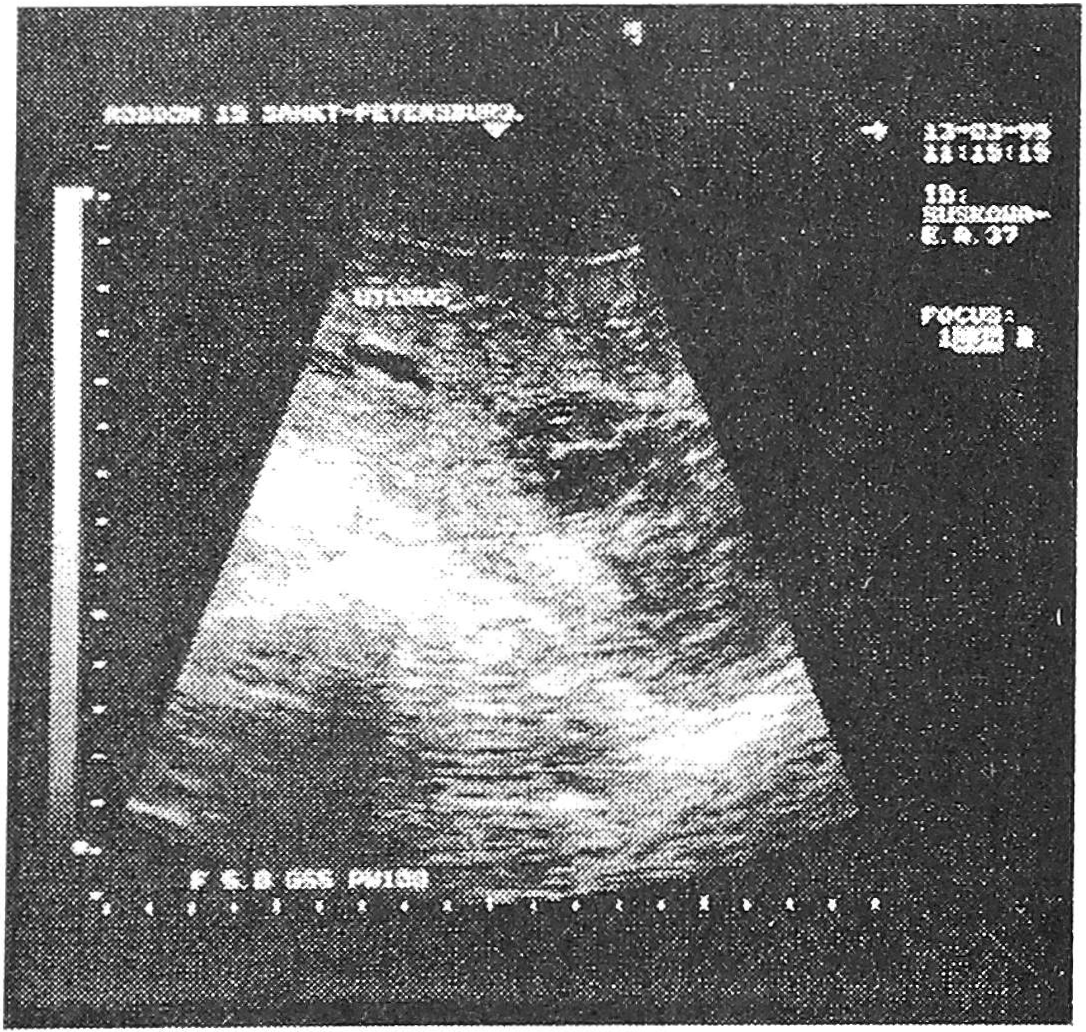

В другом случае мы наблюдали редкое осложнение после кесарева сечения - гематометру. Первобеременная первородящая 37 лет родоразрешена в плановом порядке по совокупности показаний. При этом отмечена достаточная проходимость внутренего зева и цервикального канала, что позволило вести данный случай консервативно. На эхограмме на 3-и сутки определялось неравномерное расширение полости матки, шейка не сформирована. В полости визуализируется значительное количество сгустков крови, не дающих акустическую тень (рис. 4). В динамике на 10-й день (рис. 5), сгустки определились в шейке и на выходе из нее. Полное опорожнение гематометры произошло к 16-му дню послеродового периода.

Рис. 4. Гематометра в послеоперационном периоде.

Рис. 5. Гематометра в послеоперационном периоде. Содержимое полости матки сместилось в шейку.